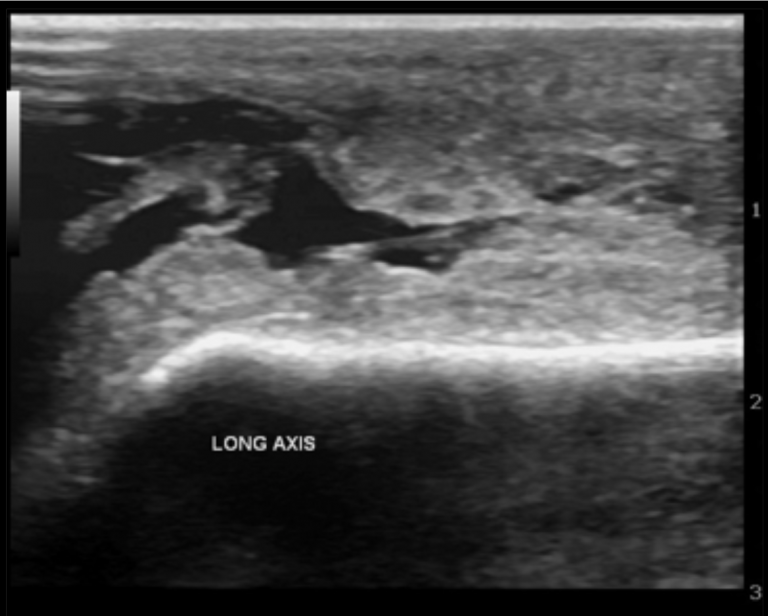

FULL TEXT Septic subacromial bursitis caused by Streptococcus

From www.ijcasereportsandimages.com

FULL TEXT Septic subacromial bursitis caused by Streptococcus Is Septic Bursitis Dangerous septic arthritis is a rare and serious condition that affects one or more of your joints. septic bursitis is uncommon and is often difficult to distinguish clinically from aseptic bursitis, cellulitis, and septic arthritis. septic bursitis is most likely to occur in bursae that lie just below the skin, such as the prepatellar bursa at the kneecap. Is Septic Bursitis Dangerous.